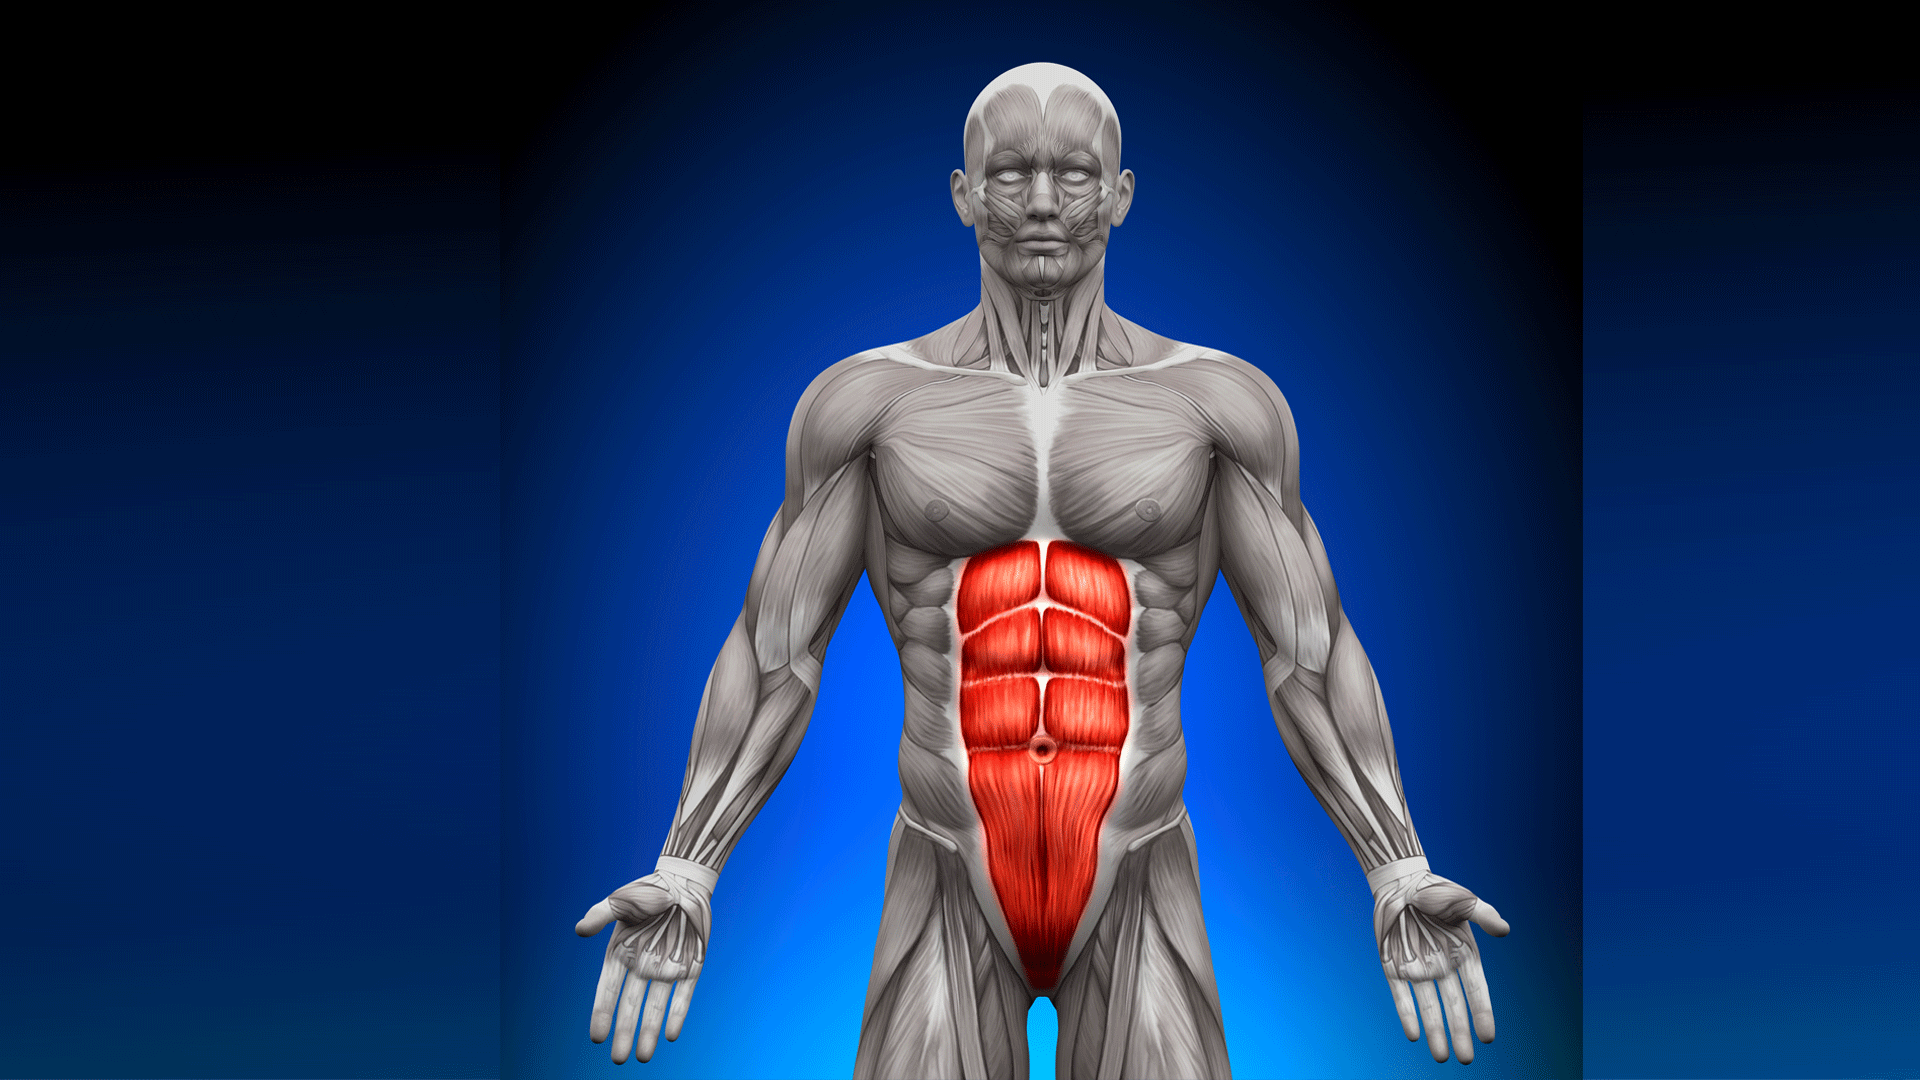

abdomen anatomy model Medically accurate illustration of the abdominal anatomy stock photo

Human Muscles Abdomen Muscles Anatomy Medical Stock Illustration

Medically Accurate Illustration Of The Abdominal Anatomy Stock Photo

www.alamy.comabdominal medically accurate

www.alamy.comabdominal medically accurate

www.dreamstime.comHD Wallpaper: 3d, 3d Illustration, 3d Rendering, Abdomen, Abdominal

www.dreamstime.comHD Wallpaper: 3d, 3d Illustration, 3d Rendering, Abdomen, Abdominal

3d Rendered Illustration Of The Abdominal Muscles Stock Photo - Alamy

www.alamy.comabdominal

www.alamy.comabdominal